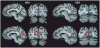

Multiple functional methods including functional magnetic resonance imaging, transcranial magnetic stimulation, and positron emission tomography have shown cortical reorganization in response to blindness. We investigated microanatomical correlates of this reorganization using diffusion tensor imaging and diffusion tensor tractography (DTT). Five early blind (EB) were compared with 7 normally sighted (NS) persons. DTT showed marked geniculocalcarine tract differences between EB and NS participants. All EB participants showed evidence of atrophy of the geniculocortical tracts. Connections between visual cortex and the orbital frontal and temporal cortices were relatively preserved in the EB group. Importantly, no additional tracts were found in any EB participant. Significant alterations of average diffusivity and relative anisotropy were found in the white matter (WM) of the occipital lobe in the EB group. These observations suggest that blindness leads to a reorganization of cerebral WM and plausibly support the hypothesis that visual cortex functionality in blindness is primarily mediated by corticocortical as opposed to thalamocortical connections.